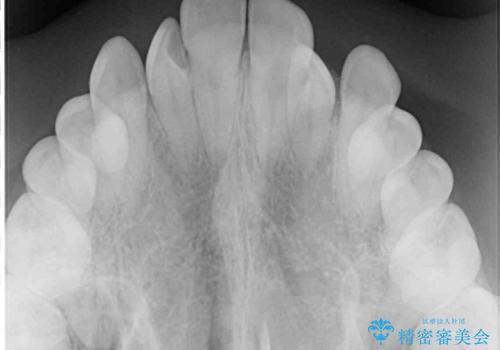

- 前歯のデコボコと、下顎の変位と受け口を気にして来院された患者様です。

初診時には大学病院にて顎の骨を切る外科矯正を勧めましたが、妥協的なゴールでも構わないので外科処置をせずに矯正を行いたいとのことでした。

まずは急速拡大装置にて上顎骨を側方に拡大し、インビザラインにて歯列と咬合を整えることとしました。